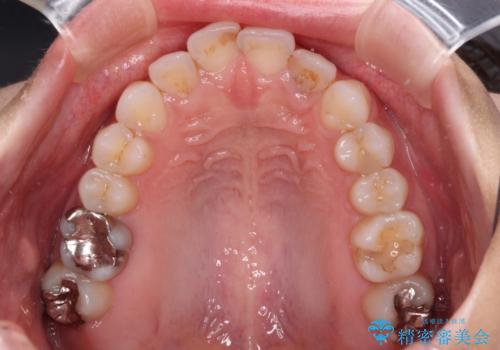

楽して短期間で歯列を整えたいとのことで、ワイヤー装置を用いて矯正治療を行い、矯正治療後に下顎の虫歯はセラミックインレー、上顎はPGAインレー(ゴールドインレー)、根管治療を行う歯についてはオールセラミッククラウンにて補綴治療を行うこととしました。

矯正治療は8ヶ月ほどで終了し、速やかに虫歯治療に移行することができました。

保険治療で用いる樹脂(コンポジットレジン)で行った虫歯治療は、周辺が変色して汚くなっていましたが、下顎はセラミックインレーで審美的に、上顎はPGAインレーで歯に負担の少ない治療を行うことができました。